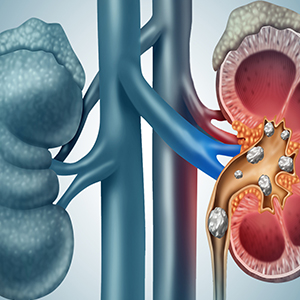

Η νεφρολιθίαση (ή «πέτρες στα νεφρά») είναι η κατάσταση κατά την οποία σχηματίζονται σκληρές μάζες (λίθοι) μέσα στους νεφρούς ή στην ουροποιητική οδό. Αυτοί οι λίθοι αποτελούνται από άλατα και ορυκτά (π.χ. ασβέστιο, οξαλικό, ουρικό οξύ).